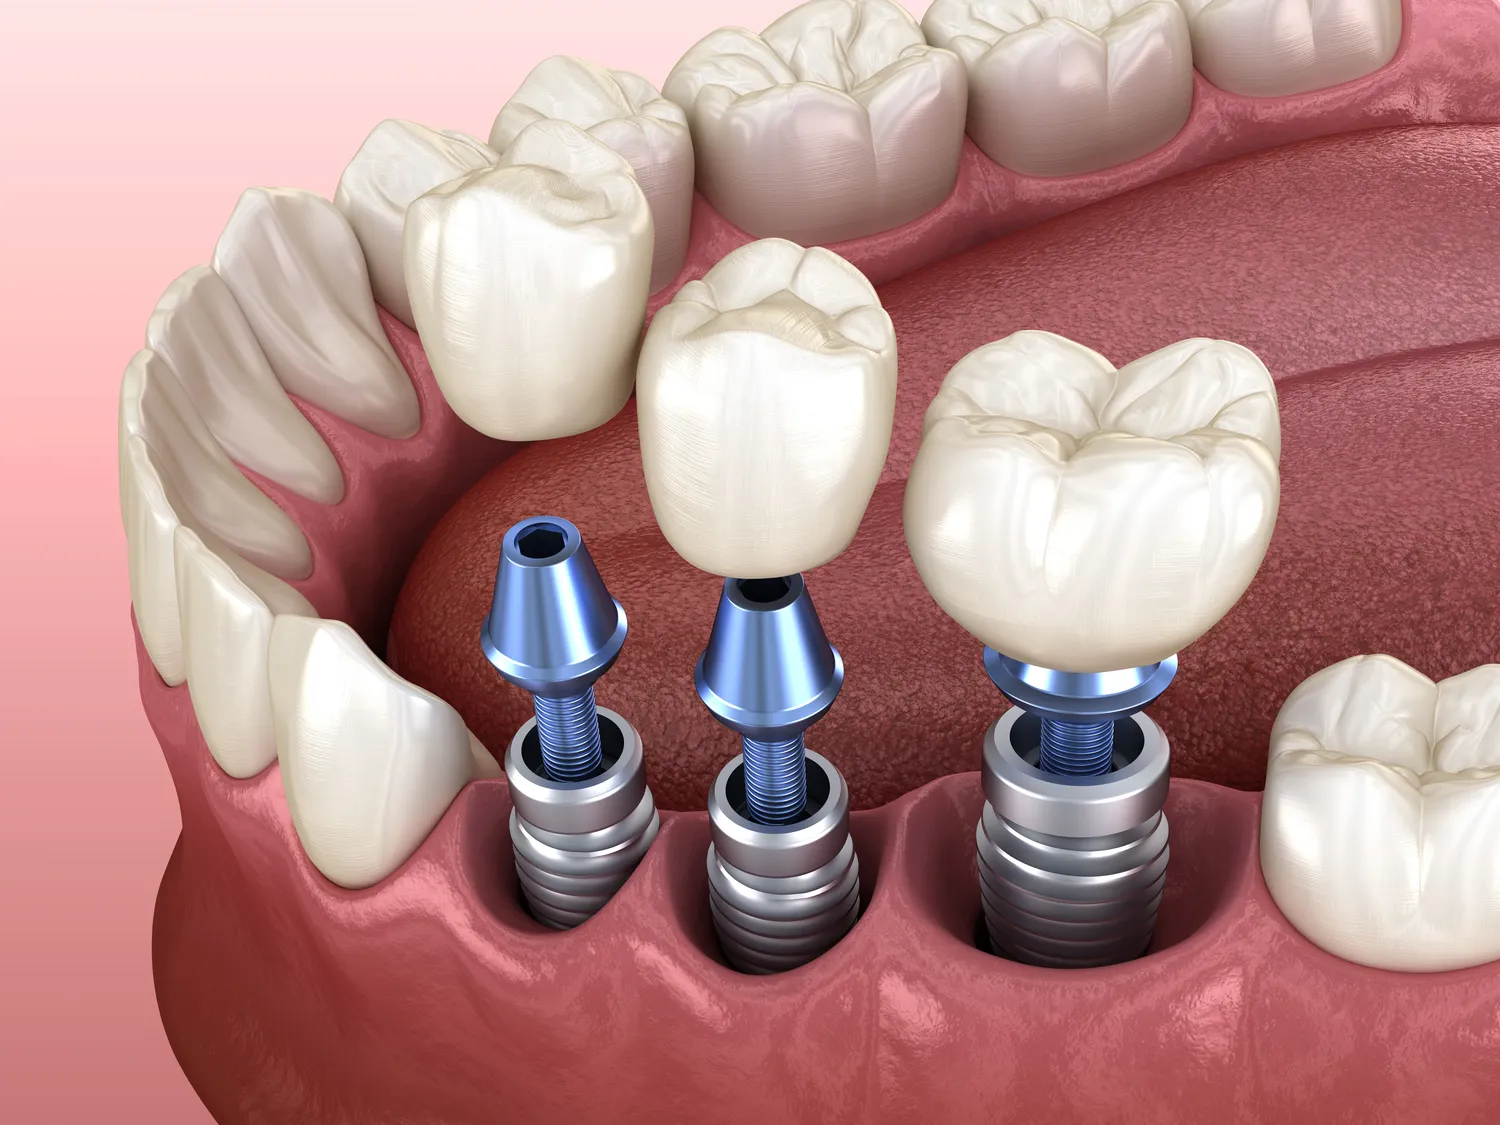

Bezśrubowe implanty to innowacyjne rozwiązanie w dziedzinie stomatologii, które zyskuje coraz większą popularność. W przeciwieństwie do tradycyjnych implantów, które wymagają użycia śrub do mocowania, bezśrubowe implanty opierają się na zaawansowanej technologii, która pozwala na ich stabilizację bez konieczności stosowania dodatkowych elementów mocujących. Działanie tych implantów opiera się na specjalnie zaprojektowanej strukturze, która umożliwia ich osadzenie w kości szczęki lub żuchwy. Dzięki temu proces gojenia jest szybszy i mniej inwazyjny. Bezśrubowe implanty są często wykonane z materiałów biokompatybilnych, co zmniejsza ryzyko odrzutu przez organizm. Warto również zaznaczyć, że ten typ implantów może być stosowany w różnych przypadkach, od pojedynczych braków zębowych po bardziej skomplikowane rekonstrukcje całych łuków zębowych.

Różnice między bezśrubowymi a tradycyjnymi implantami są znaczące i dotyczą zarówno samego procesu wszczepienia, jak i późniejszego użytkowania. Tradycyjne implanty wymagają zastosowania śrub do mocowania ich w kości, co może wiązać się z większym ryzykiem powikłań oraz dłuższym czasem gojenia. W przypadku bezśrubowych implantów nie ma potrzeby stosowania dodatkowych elementów mocujących, co sprawia, że procedura jest prostsza i szybsza. Kolejną różnicą jest materiał użyty do produkcji tych implantów – bezśrubowe wersje często korzystają z nowoczesnych kompozytów lub tytanu o wysokiej biokompatybilności. Różnice te wpływają także na komfort noszenia – pacjenci często zauważają, że bezśrubowe implanty są mniej odczuwalne w jamie ustnej i lepiej integrują się z naturalnymi tkankami. Warto również wspomnieć o estetyce – bezśrubowe implantu mogą oferować lepsze dopasowanie do kształtu i koloru naturalnych zębów, co przekłada się na bardziej naturalny wygląd uśmiechu.

Proces wszczepienia bezśrubowych implantów jest zazwyczaj mniej skomplikowany niż w przypadku tradycyjnych rozwiązań. Na początku pacjent przechodzi szczegółową konsultację stomatologiczną, podczas której lekarz ocenia stan zdrowia jamy ustnej oraz wykonuje niezbędne badania obrazowe, takie jak zdjęcia rentgenowskie czy tomografia komputerowa. Te badania pozwalają na dokładne zaplanowanie zabiegu oraz określenie optymalnego miejsca dla implantu. Po przygotowaniach następuje właściwy zabieg, który często odbywa się w znieczuleniu miejscowym. Lekarz wykonuje niewielkie nacięcie w dziąśle, aby uzyskać dostęp do kości, a następnie osadza implant w odpowiednim miejscu. Dzięki nowoczesnym technologiom, takim jak cyfrowe planowanie i nawigacja, możliwe jest precyzyjne umiejscowienie implantu, co zwiększa jego szanse na sukces. Po wszczepieniu implantu pacjent otrzymuje zalecenia dotyczące pielęgnacji oraz diety w okresie gojenia. Warto podkreślić, że czas gojenia może się różnić w zależności od indywidualnych predyspozycji pacjenta oraz jakości tkanki kostnej.